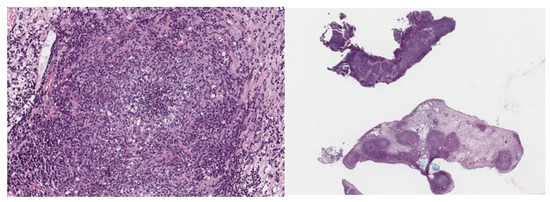

3.2. Case 2